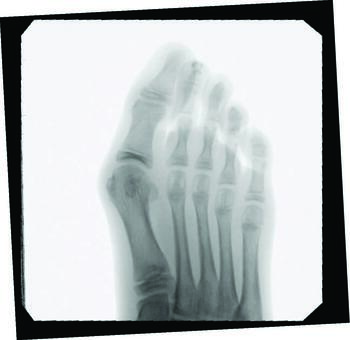

When we approach surgical correction of hallux valgus, goals include realigning the hallux joint across all three planes, improving the first intermetatarsal angle, restoring and maintaining a pain-free joint, improving cosmesis, and allowing a return to comfortable shoes. Inclusion criteria for surgery that we consider include intact vasculature, Vitamin D-25 levels above 40 nmol/dl, and medical stability in the presence of comorbidities. Percutaneous hallux valgus correction has indication for spastic or non-spastic bunions, revisions, and a wide range of intermetarsal angles. Other exclusion considerations include patients with severe osteoarthritis or osteomyelitis near the first metatarsophalangeal joint.

In a study comparing MIS to distal chevron metatarsal osteotomy bunion correction in a population of young females, there were no statistically significant outcomes in postoperative radiographic measurements of hallux valgus angle, DMAA, sesamoid position, first metatarsal length, and relative second metatarsal length.15 Clinical scores significantly increased postoperatively in both groups, with higher cosmesis satisfaction rates and a shorter operative time in the MIS group. This study found that the most significant complication in the MIS group was revision due to osteotomy site irritation occurring about three months postoperatively, while deformity correction was necessary two years postoperatively in the chevron group.15

Kaufmann and colleagues compared five-year outcomes of open distal metatarsal chevron osteotomies to a minimally invasive approach, finding comparable satisfaction as well as radiographic and clinical outcomes in both groups.16 More recently, Neufeld and team reported that the minimally invasive chevron and Akin (MICA) procedure achieves reproducible significant correction and high patient satisfaction with early weight-bearing and fast pain score improvement.13 They noted a 5.3 percent reoperation rate due to hardware removal, debridement, and neurolysis, finding no significant increase in nerve injury between the MICA and open procedure groups. The authors also noted significant deformity correction is possible with the third-generation approach of utilizing two bicortical screws.13

Over the last decade, I, the senior author, have performed hundreds of bunion procedures through both traditional and minimally invasive approaches. My criteria for surgical candidacy for MIS procedures started in the high-risk wound population with multiple comorbidities, including patients with diabetes, human immunodeficiency virus (HIV), acquired immunodeficiency syndrome (AIDS), rheumatoid arthritis (RA), and transplant recipients. All of these populations of patients are at higher risk for surgical complications, such as infections and wound and bone healing delays. My outcomes and results in these patients were so remarkable that I then expanded my criteria to include healthier and higher-demand populations, including children and athletes. In my experience, this surgical approach can help address a complex deformity in the young population, decreases postoperative rehabilitation, improves function, and avoids disrupting a child’s open growth plate. All possible without leaving hardware behind.